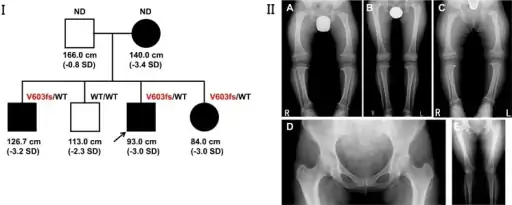

Unlike other "rickets syndromes", affected individuals have normal serum calcium, phosphorus, and urinary amino acid levels. Long bones are short and curved, with widened growth plates and metaphyses.[5]